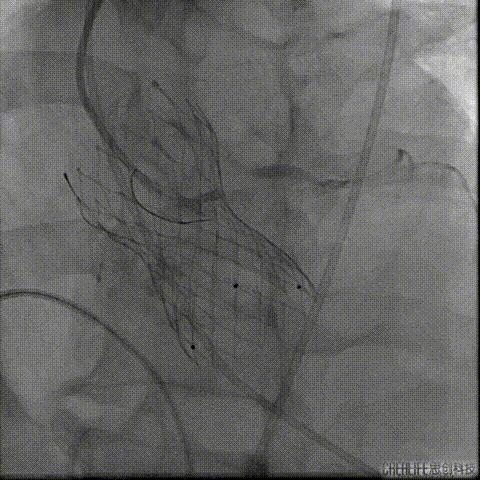

TAVR术后3日Hb较前下降 (63g/L)

CT提示左侧腹膜后、髂窝及腹股沟区巨大血肿

行急诊手术 腹主动脉及左侧股动脉造影

左侧股动脉见造影剂外渗

球囊压迫后植入覆膜支架

复查造影